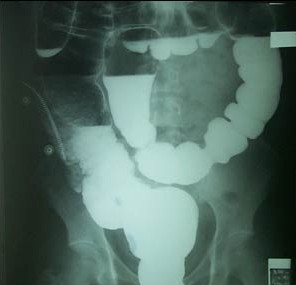

当怀疑病人有结直肠的某些疾病(比如梗阻溃疡肿瘤等)时,便可采用此法。采用钡剂灌肠,从肛门注入稀释钡剂然后再打入少量气体,使得直肠、全部结肠及盲肠显影。 然后通过射线排除制剂在体内形成的形态变化来确定是否有占位及溃疡性疾病的一种方法、钡剂高密度,在射线通过时显白影,周围组织黑色,对比明显,容易分别。

包括单纯性钡剂灌肠气钡双对比造影。前者仅用于评价有梗阻、瘘道的患者;后者为目前最常用的大肠x线检查,它能观察粘膜表现和检出微小病变, 可用于检查大肠各种占位性病变(大肠癌)、炎症性病变、憩室、肠气囊肿症、肠套叠以及先天性巨结肠等疾病。

钡灌肠前几分钟,肌肉注射抗胆碱药(可使大肠的平滑肌充分松弛)。再逆行灌注稀钡1000ml左右,同时注入适量空气(300ml左右)。此法同时在钡、气的双重显示下,能够发现微小病变,更能充分显示病变的形态、大小、边缘等。